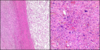

Elderly person, bedridden, near sacrum

Ischemic fasciitis

- Benign, reactive

- Fibrinoid necrosis is key

- Usually not well circumscribed

- Fibroblastic/myofibroblastic, ganglion like cells

- Ganglion-like cells characteristic

- AKA atypical decubital fibroplasia

Young adult with HIV.

S-100 and CD68 positive.

Mycobacterial Spindle Cell Pseudotumor

- Spindled lesion

- Vesicular, oval cells w/ indistinct cell borders

- Vaguely storiform

- Scattered giant cells

- Stains:

- SMA, FLY1, ERG -

- Desmin -

- CD31/34 -

- HHV8 -

- CD3/20 -

- CD68 +

- CD163 +

- AFB +